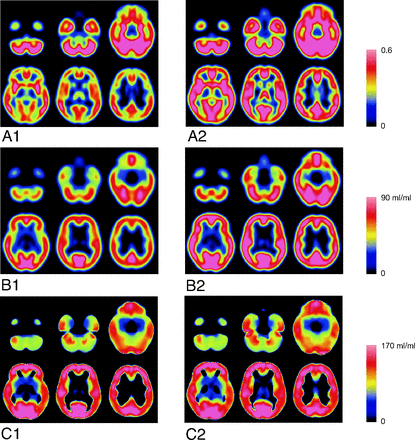

In a comparison of the averaged images between the young and elderly subjects, though the age-related decrease of the rGMC and PVE-uncorrected BP were similar (Fig 5A, -B), no age-related changes were found in the PVE-corrected BP (Fig 5C). The SPM multiple regression analysis for the PVE-corrected BP images showed no significant age-related changes of the BP, even when a liberal cutoff threshold (P < .1 with false discovery rate correction) was used.

Normalized and averaged images of rGMC and I-123 iomazenil BP. A1, rGMC image of elderly subjects. A2, rGMC image of young subjects. B1, PVE-uncorrected BP image of elderly subjects. B2, PVE-uncorrected BP image of young subjects. C1, PVE-corrected BP image of elderly subjects. C2, PVE-corrected BP image of young subjects.